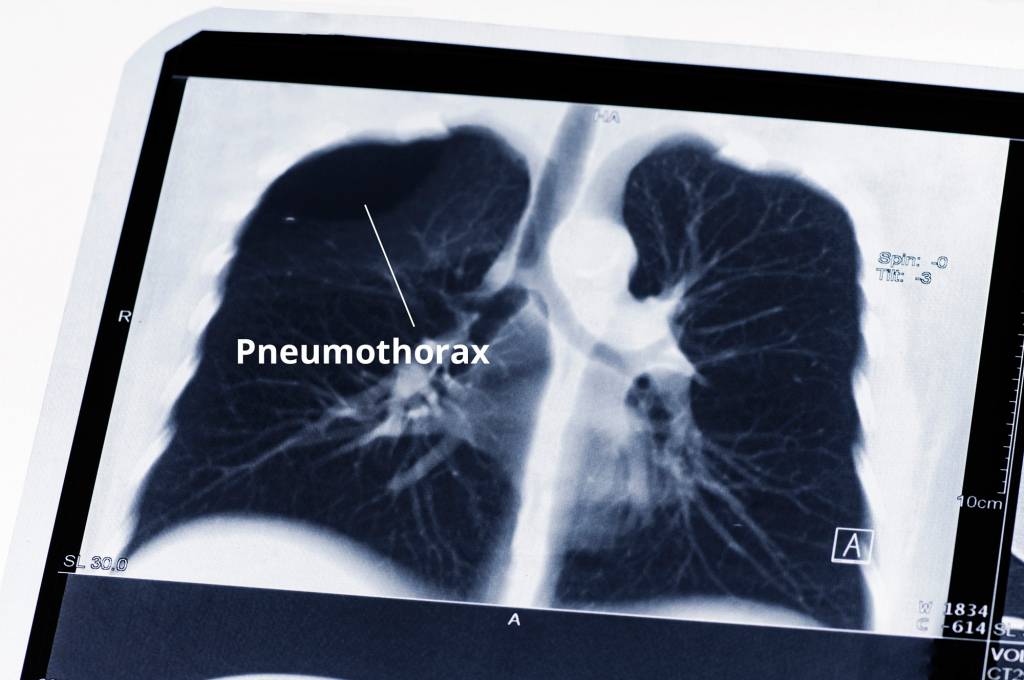

Unter Umständen kann es beim Schlüsselbeinbruch sogar zu einer Verletzung der Lunge mit möglichen Atemproblemen (etwa beim Pneumothorax = Zusammenfallen eines Lungenflügels) kommen.

Auf dem Röntgenbild ist der Knochenbruch meist gut zu sehen. Im Zweifelsfall kann eine Computertomographie (CT) angefertigt werden. Eine Kernspintomographie (MRT, Magnetresonanztomographie) kann aufdecken, ob sich weitere Schäden an Gelenken oder Bändern ergeben haben.